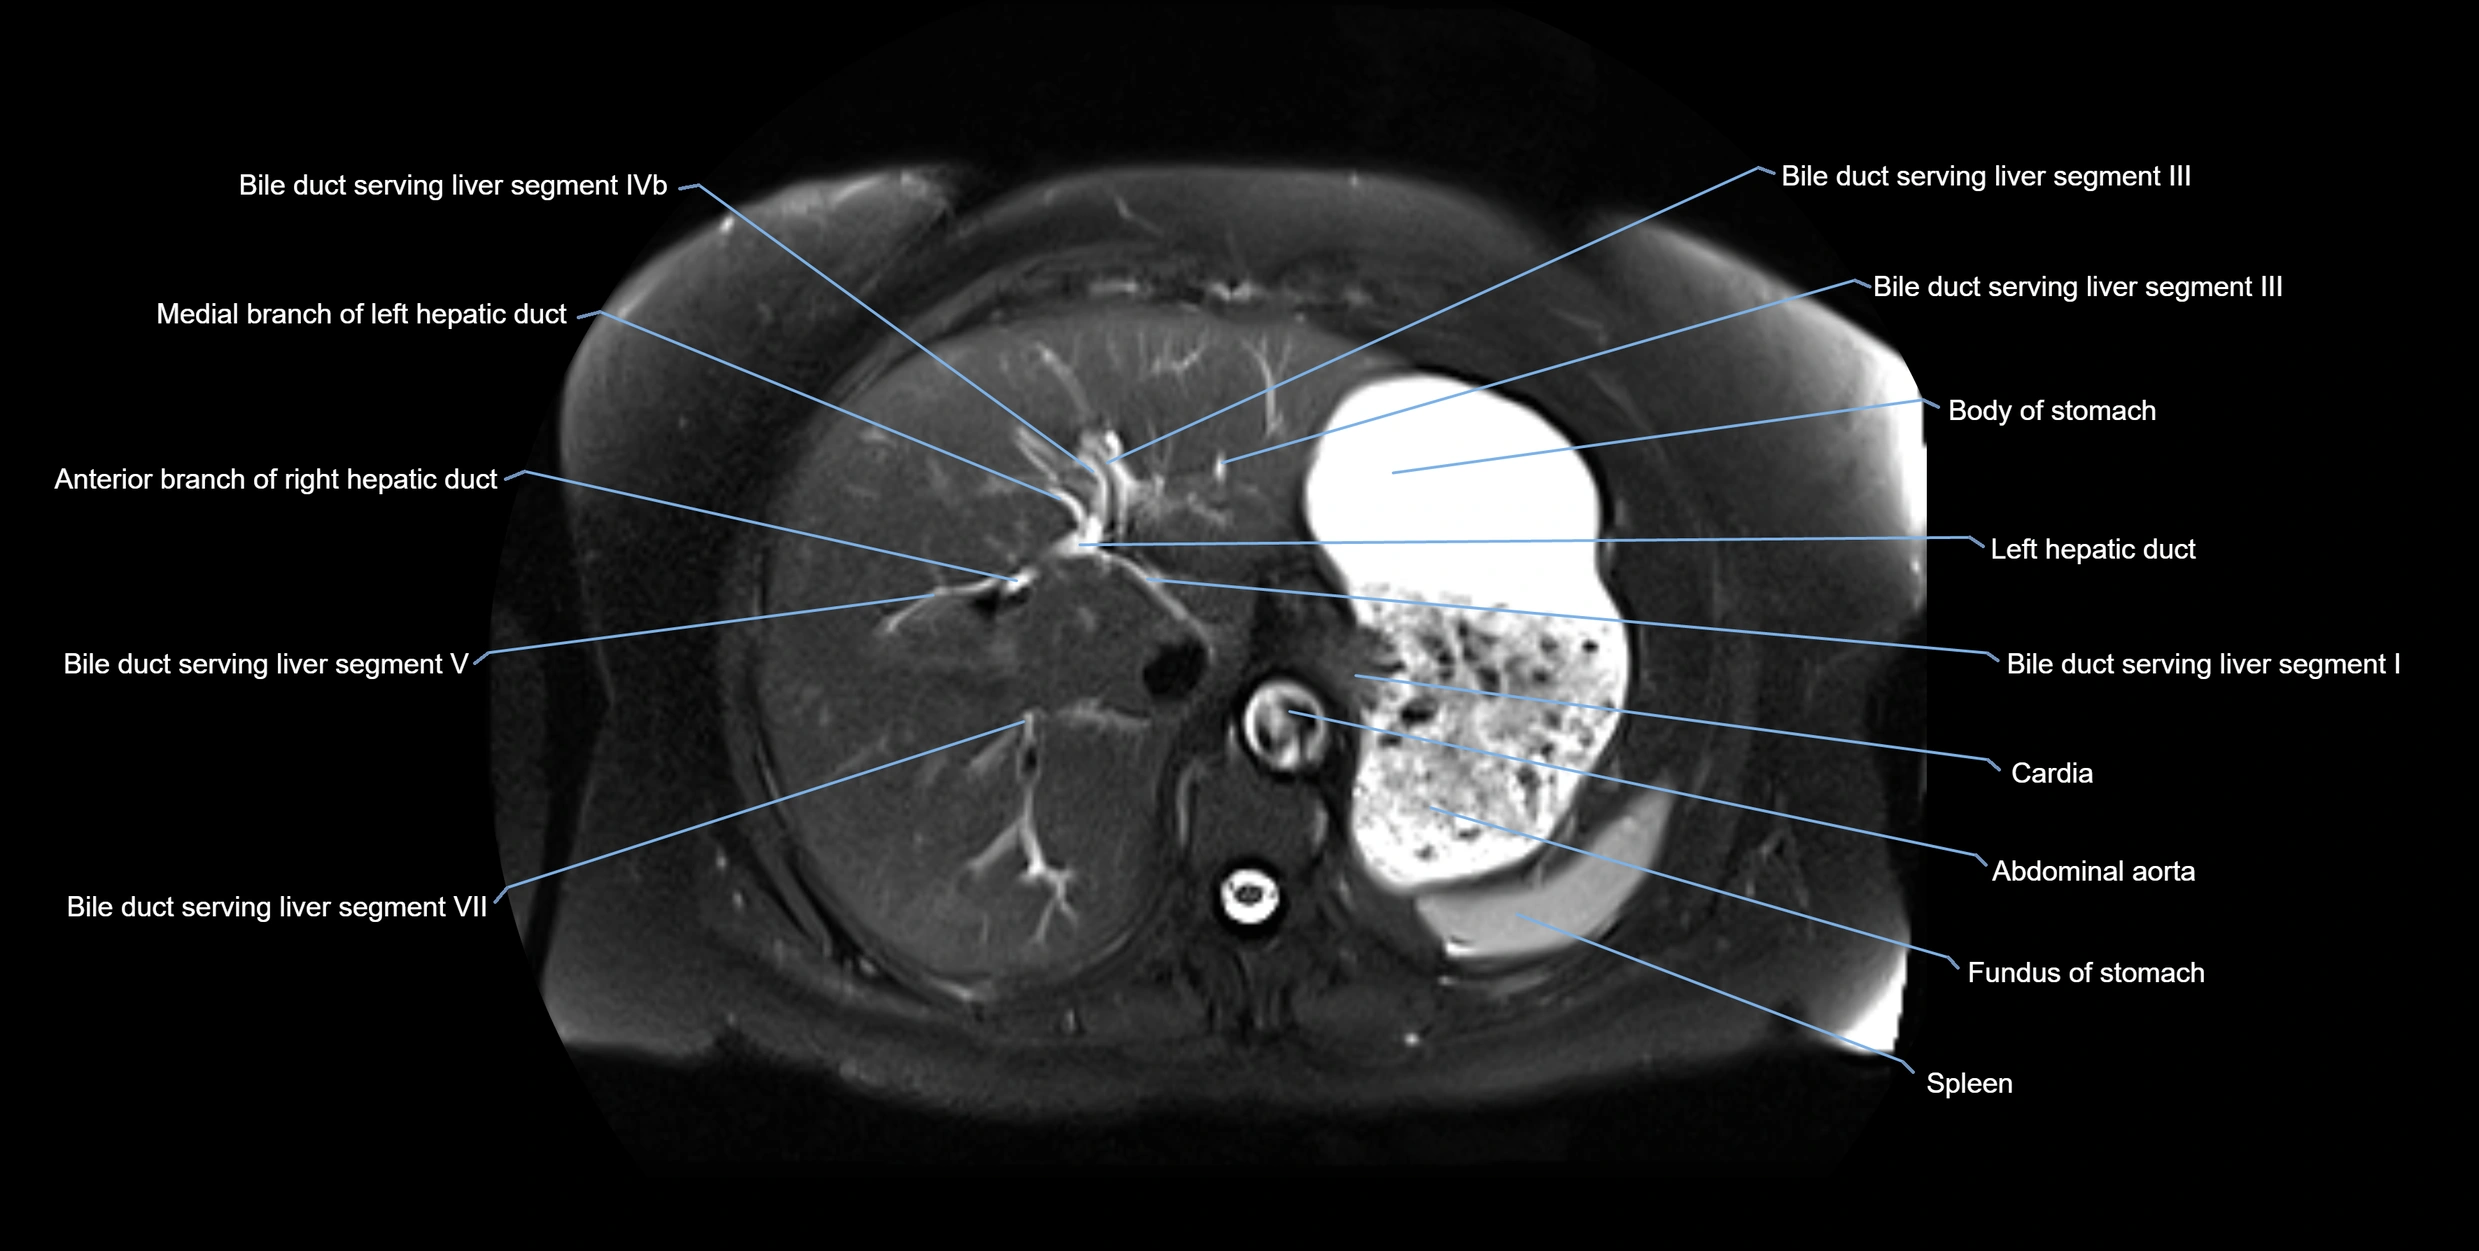

MRI image

image